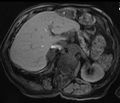

| ورم غدي كظري في مريض مصاب بمتلازمة كون | |

عادة ما يوصف ورم القشرة الكظرية الغدي بأنه ورم حميد ينشأ من الخلايا التي تتكون منها قشرة الغدة الكظرية . مثل معظم الأورام الغدية ، يعتبر ورم القشرة الكظرية الغدي ورمًا حميدًا لأن معظمها لا يعمل ولا تظهر عليه أعراض . تصنف أورام القشرة الكظرية الغدية على أنها اضطرابات مستقلة عن الهرمون الموجه لقشر الكظر ، وترتبط عادةً بالحالات المرتبطة بفرط الكظر مثل متلازمة كوشينغ ( فرط الكورتيزول ) أو متلازمة كون ( فرط الألدوستيرونية) ، والتي تُعرف أيضًا باسم الألدوستيرونية الأولية ..[1] بالإضافة إلى ذلك ، تدعم تقارير الحالات الحديثة ارتباط أورام قشر الكظر الغدية بفرط الأندروجين أو فرط الأندروجين الوردي الذي يمكن أن يسبب كثرة الشعر عند الإناث..[2] تختلف "متلازمة كوشينگ " عن " مرض كوشينگ " على الرغم من أن كلا الحالتين ناتجة عن فرط الكورتيزول. يشير مصطلح " مرض كوشينگ " تحديدًا إلى "فرط الكورتيزول الثانوي" المصنف على أنه " متلازمة كوشينغ المعتمدة على الهرمون الموجه لقشرة الكظر " الناتجة عن أورام الغدة النخامية الغدية . في المقابل ، تشير "متلازمة كوشينگ" تحديدًا إلى "فرط الكورتيزول الأولي" المصنف على أنه " متلازمة كوشينغ المستقلة عن الهرمون الموجه لقشرة الكظر " الناتجة عن أورام الغدة الكظرية الغدية.